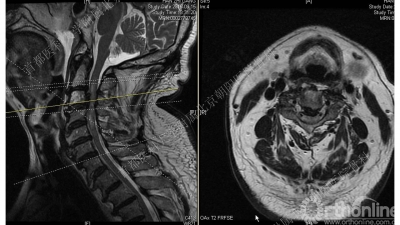

术前MRI:C3-4椎体后缘低信号团块影,边界清晰,对应节段脊髓受压

CT是诊断后纵韧带骨化的金标准,通过CT矢状位重建有助于辨别骨化块的大小和形状以及椎管狭窄的程度。

MRI用于评估颈脊髓损伤的严重程度以及观察颈脊髓内的病变。